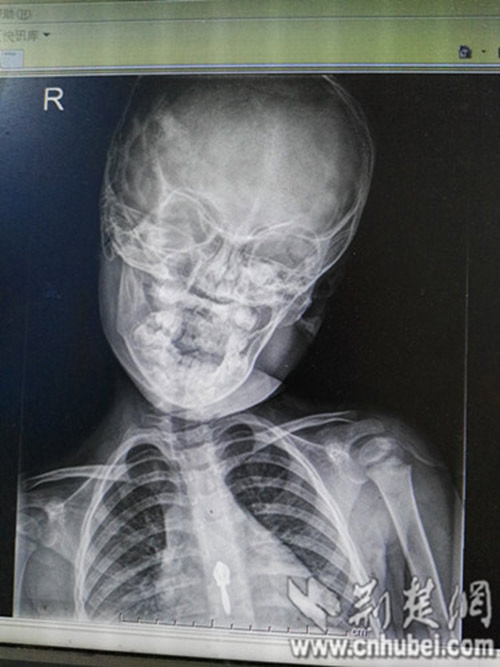

Theo một bài viết được chia sẻ "chóng mặt" trên trang Sports Network (Trung Quốc), sau khoảng 1 năm đều đặn sử dụng điện thoại và máy tính bảng, một bé gái 3 tuổi đã phải nhập viện khẩn cấp và trở thành bệnh nhân "nhí" tại khoa Phục hồi chức năng để điều trị bệnh lệch cổ, thoái hóa đốt sống cổ.

Theo bác sĩ Hồ Tiểu Quân, giám đốc bệnh viện Phổ Nhân, trẻ em trong một thời gian dài ngồi yên một chỗ để chơi iPad, điện thoại di động sẽ gây ra đau cơ cổ, căng thẳng, co thắt dây chằng, nếu không can thiệp, nguy cơ trong tương lai sẽ bị thoát vị đĩa đệm cổ và các bệnh khác.

Hiện tượng này cũng xảy ra phổ biến và lứa tuổi ngày càng nhỏ. Không những thế, thoái hóa đốt sống cổ ở trẻ em còn gây nguy hiểm lớn hơn rất nhiều so với người lớn, và thiệt hại đối với cuộc sống của trẻ là không hề nhỏ.

Ngoài ra, xương của trẻ em đang trong giai đoạn phát triển, căn bệnh này có thể ảnh hưởng đến kích thước của đốt sống cổ, phát triển dị dạng, trường hợp nghiêm trọng thậm chí có thể ảnh hưởng đến ngực, thắt lưng và các phần xương khác, thậm chí làm hạn chế phát triển chiều cao.